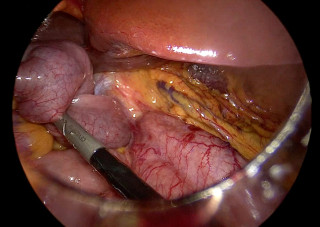

Case presentation

A 31-year-old previously healthy woman, with no surgical history, presented with sudden-onset, severe peri-umbilical abdominal pain unresponsive to high-dose opioids. CT-scan revealed mildly dilated distal jejunum with mesenteric edema and free fluid (Fig. 1, 2). Because of persistent pain despite step III analgesia, emergency diagnostic laparoscopy was performed. Intraoperatively, a closed-loop obstruction of an ileal segment was identified, herniated through a narrow internal window formed by an adherent mesenteric vessel supplying a Meckel’s diverticulum (Fig. 3). The vascular band was divided, releasing the closed loop, with no irreversible small bowel ischemic damage. The Meckel’s diverticulum was resected. The post-operative course was uneventful, and the patient was discharged after two days.